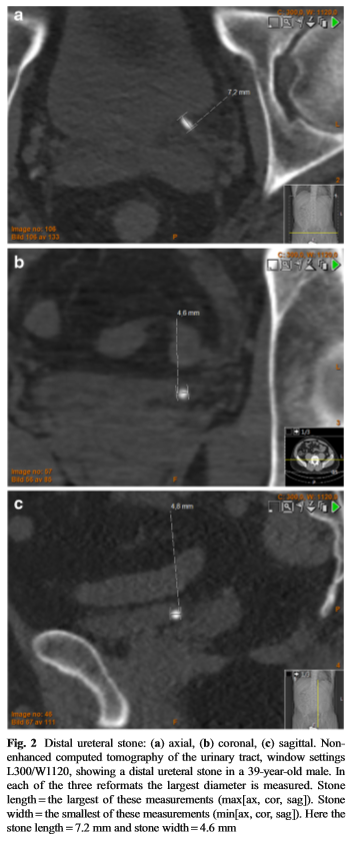

축상, 관상, 시상 면에서 크기를 재어 가장 긴(최장), 가장 짧은(최단) 직경을 분석하였다.

2017년 12월 European Radiology에 게재된 논문입니다. 이 논문은 요관 결석 의 자동화된 삼차원 크기 측정법과 영상의학과 의사에 의한 수동 측정법이 자연 배출 예측에 차이가 있는지, 그리고 단순한 직경 측정법과 부피 측정법이 예측에 차이가 있는지 알아본 내용입니다. 391명을 대상으로 마찬가지로 조영하지 않은 CT로 평가 하였고, 요관 결석의 축상, 관상, 시상면 직경을 측정하였습니다. 수동 측정은 3명의 영상의학과 의사가 하였고(최종적으로 최장, 최단 직경 3명의 평균값을 분석) 자동화 프로그램은 Mathworks사 프로그램으로 직경과 면적, 부피 등을 측정 했습니다. 모든 환자는 4주/20주로 나누어서 자연 배출 여부를 확인했습니다.